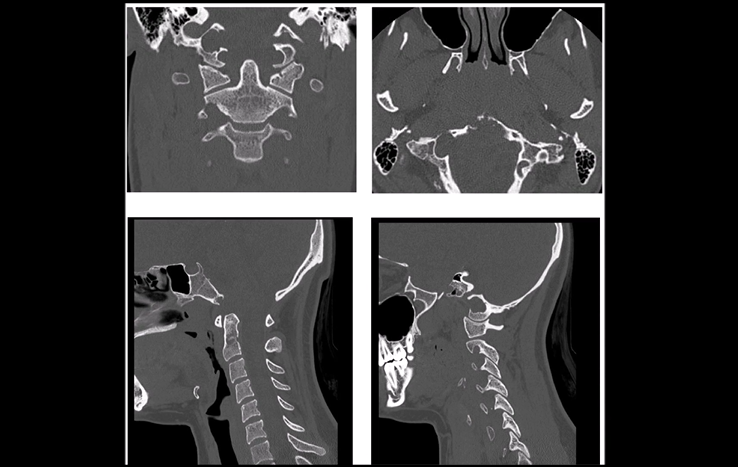

CT显示下斜坡和右侧枕骨髁部分损害